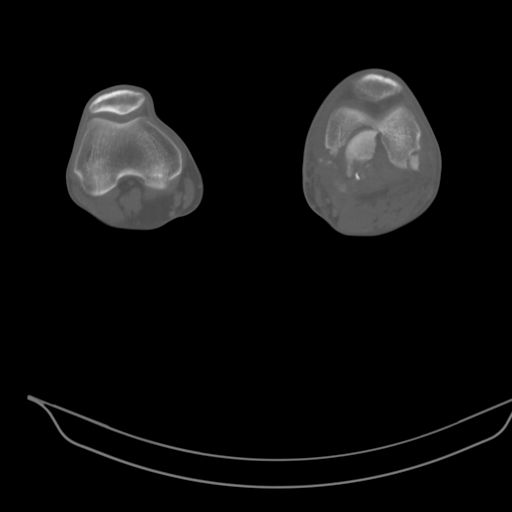

Качественные только исходные рентгенограммы (вышлю или завтра или в понедельник). Все последующие рентгенисследования были малоинформативны

(в т.ч. и последние снимки). КТ-исследование делалось 3 или 4 дня назад...

This is a coronal split in the femoral condyle and is a rare injury. Please see attachment for ORIF result

CT shows major bony fragments which are markedly rotated .With this amount of bony damage,you probably should attempt to get reasonably loooking knee with ORIF and thn if he needs a TKR due to pain a few years from now, then tleast you have something looking like a knee that you can replace rather than having to use revision knee for a primary TKR now. 4 weeks is not too long .what is the condition of soft tissues?

При внутрисуcтавных переломах трехмерные (3D) изображения, кроме красивого снимка, не дают полную информацию о состоянии отломков, самыми информативными являются корональные срезы на КТ и обычная длинная ренгенограмма конечности для сравнения оси конечности.

Фронтальные внутрисуставные переломы мыщельков бедра, так называемые Hoffa fracture, не частые, но встречающиеся переломы, в основном они связаны с травмой высокой энергией.